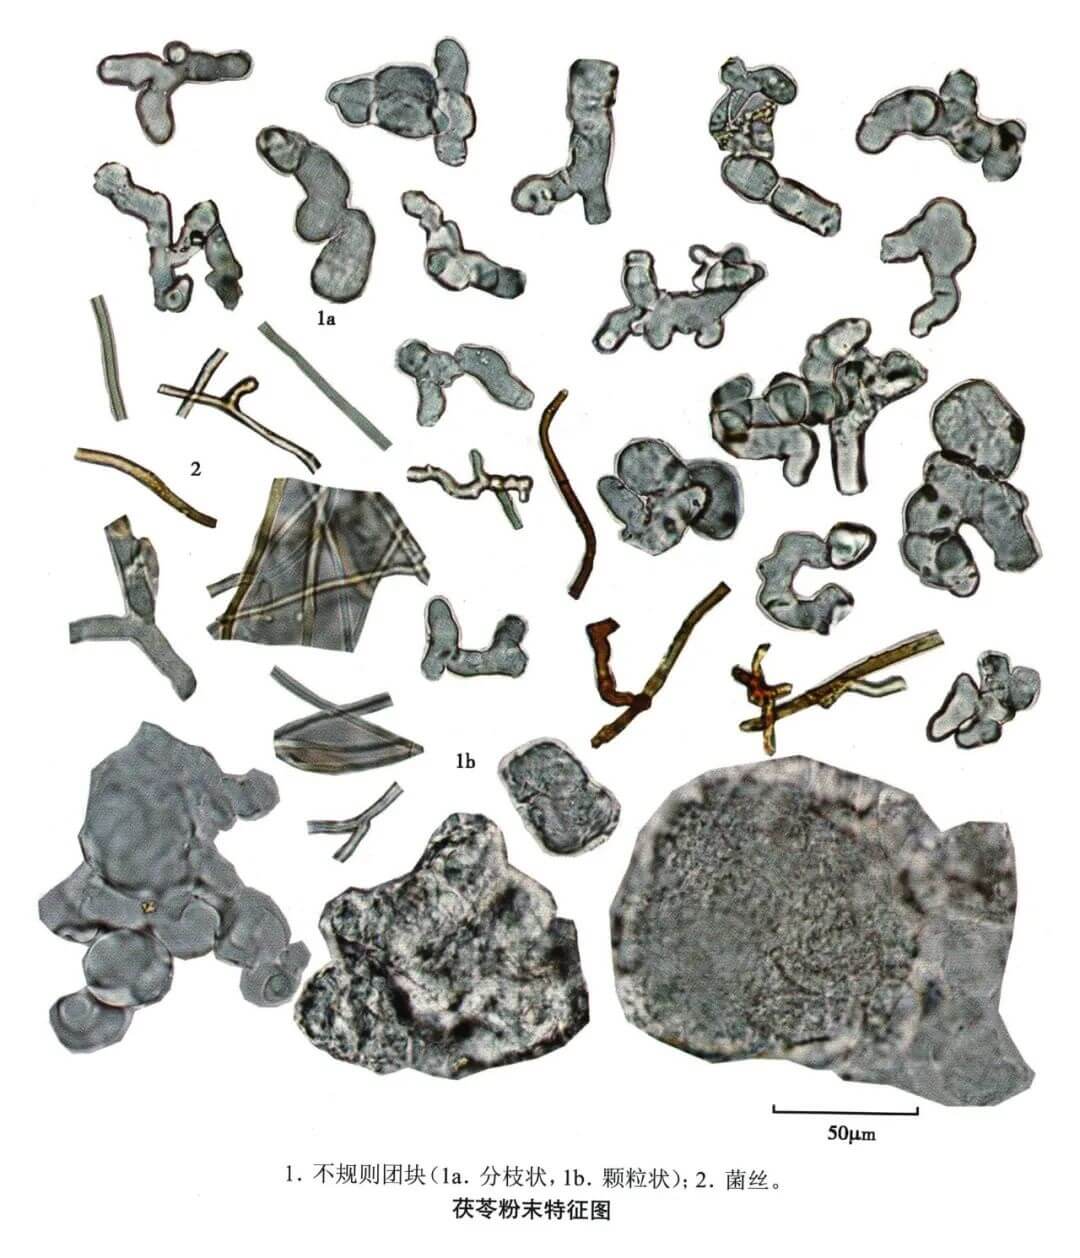

茯苓

| 茯苓 |

|---|

| 【参考标准】 《中国药典》2020年版 一部 |

| 【显微鉴别】 粉末灰白色。用水或稀甘油装片,可见无色不规则颗粒状团块或末端钝圆的分枝状团块;5%氢氧化钾液装片,则团块溶化露出菌丝。菌丝细长,稍弯曲,有分枝,无色或带棕色(外层菌丝),直径3~8μm,稀至16μm,横壁偶可察见。 |

| 本品不含淀粉粒及草酸钙晶体。 |

| 【显微重点】 菌丝团块、菌丝。5%氢氧化钾液装片才能将菌丝团块溶解,此后才能看到菌丝。 |

| 【图谱来源】 《中药成方制剂显微图典》 |